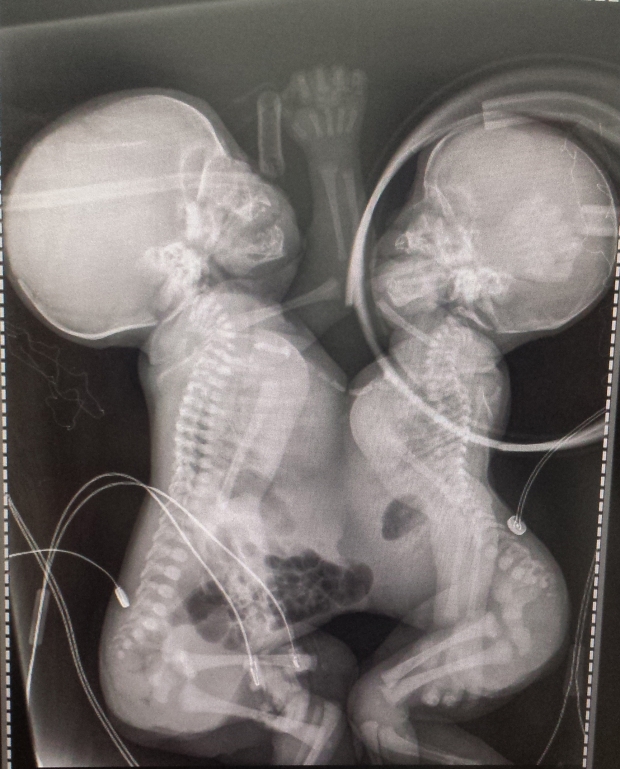

Anny Gabrielly e Anny Beattriz estão na UTI e respiram com auxílio de aparelhos. Irmãs nasceram com 37 semanas e são unidas pelo tórax e abdômen, compartilhando o coração e o fígado

Elas estão internadas na Unidade de Terapia Intensiva (UTI) Neonatal do hospital e respiram com auxílio de oxigênio suplementar. As crianças nasceram com 37 semanas e são unidas pelo tórax e abdômen, compartilhando o coração e o fígado.

Abaixo, foto do raio-x, concedida pelo hospital: